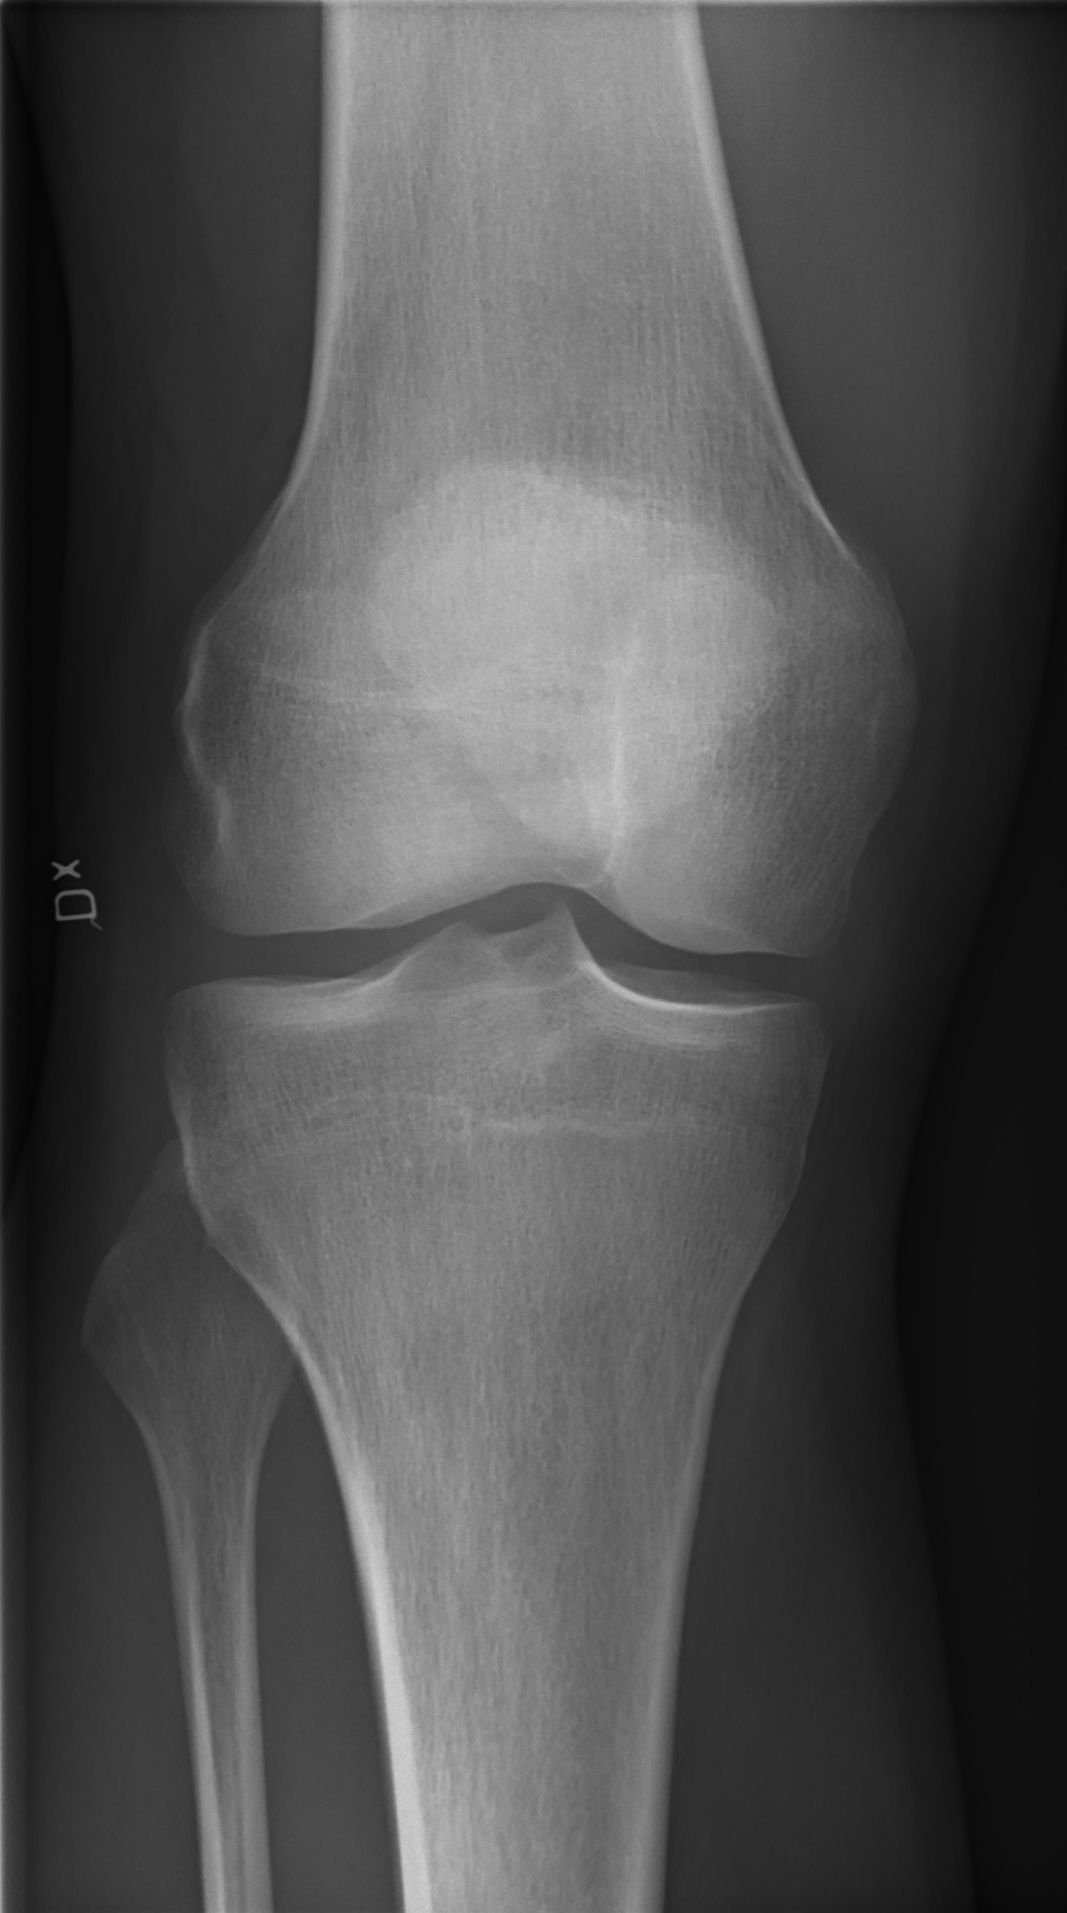

관절이 안좋을때

관절이 안좋을때 어떻게 해야 할까요?

슬관절을 유지하고 지탱해주는 가장 중요한 근육인 대퇴사두근의 강화 재활운동이 필수적이며,

재발을 막기 위해서는 증상을 일으킬 수 있는 동작을 피해야 한다.

초기에는 안정시키면서 더운 물 찜질 등을 하고 안정가료를 한다.

그리고 어느 정도 좋아지면 관절에 심한 압박이 가지 않도록 주의해야 한다.

쪼그리고 앉거나 등산, 계단 오르내리는 것을 가급적 피하고(90도 이상 구부러지지 않도록),

대퇴사두근을 강화시키는 운동을 하면 좋다.